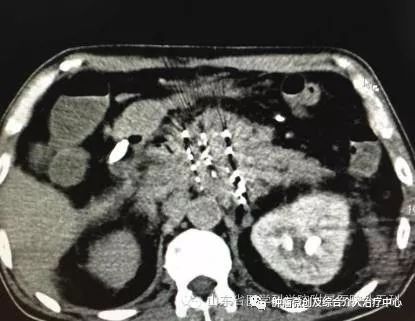

胰腺癌是消化系统常见肿瘤之一,恶性程度高,临床症状缺乏特异性,难以获得早期诊断,是目前预后最差的癌之一。以手术为主的综合治疗是其治疗原则,但由于手术切除率低,术后生存时间短,5年生存率<10%

介入治疗是目前治疗胰腺癌的一种重要方法与外周静脉化疗比较,介入治疗可以显著提高化疗药物在肿瘤组织中的浓度,不良反应小,可以更有效地抑制肿瘤细胞的生长,在减轻中晚期胰腺癌患者的临床症状、延长其生存时间、提高生活质量方面有着重要的作用。

随着介入治疗理论研究的深入、技术的进步和操作的完善,胰腺癌的介入治疗也得到了长足的发展。己经有各种不同方式的介入治疗方法用于胰腺癌的临床治疗,并取得满意疗效。介入治疗可以有效抑制肿瘤的生长,显著提高晚期胰腺癌患者的生活质量,缓解临床症状,延长生存期。目前临床应用最为广泛的是经 动脉导管灌注治疗及局部放射性碘125粒子植入治疗,而基因导向介入治疗则是当前研究的热点。基因治疗可以从根本上切断肿瘤的异常生长通路,改变其生物学行为,己有大量研究证实其有效性。倘若基因治疗能获得突破性的进展,一定会给胰腺癌的治疗带来曙光。